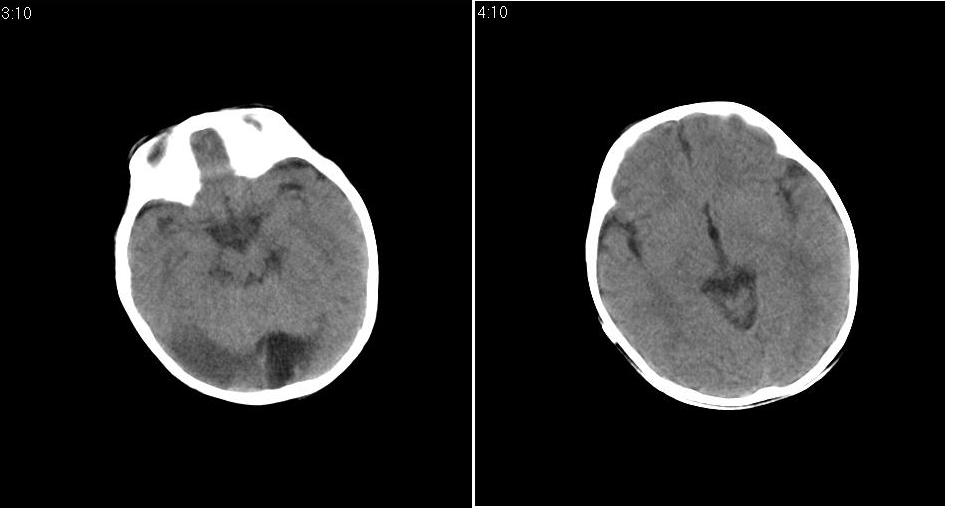

男 1岁,外伤就诊。智力正常,骨窗正常。

正常变异,大枕大池。鉴别:蛛网膜囊肿、双侧小脑发育不良。

蛛网膜囊肿一般是封闭的空间,张力较大,临近颅骨一般受压变薄。本例支持大枕大池

大枕大池与蛛网膜囊肿的主要区别就是看颅骨有没有压迹,如果有的话一般考虑蛛网膜囊肿。